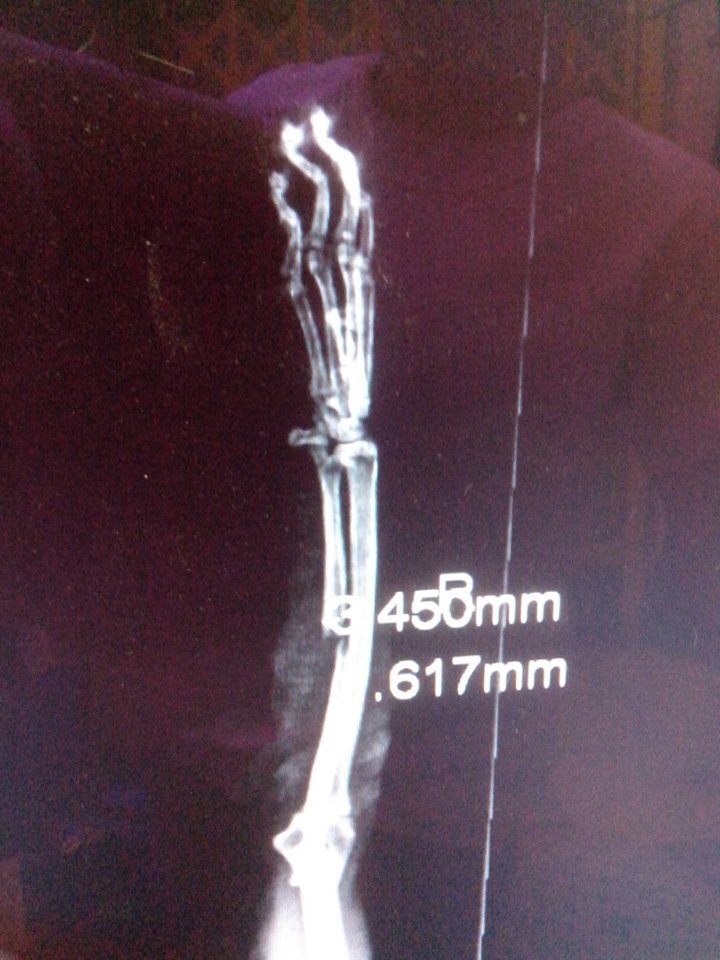

主題: 右前腳骨折的已結紮公貓-抓抓 申請者姓名: 程修芳 花色: 申請日期: 2013-11-02 08:36:06 申請者部落格: 申請者臉書網址: 所在縣市/合作醫院: 台南市/啄木鳥動物醫院 治療費用: 15970元 需求人數: 17人 已結案 (2014-01-10 18:02:14) 報名人員: ChiouYueh Shyu、Hui - Lan Zhuang(已付款)、ERic YU(已付款)、周小蕾(已付款)、WeiLin Chen(已付款)、WeiMin Lin(已付款)、Sky Lin(已付款)、謝小馬(已付款)、00(已付款)、Candace Shiue(已付款)、ginatw(已付款)、Helen Saroja Chen(已付款)、邱小祈(已付款)、nicole chen(已付款)、邱小祈、周星星(已付款)、周星星、Even Chen(已付款)、SASA(已付款)、小可(已付款)、 候補人員: 動物病情說明: 昨日發現自家附近已結紮公貓走路時右前腳一拐一拐的,因為抓抓很親人可以摸,所以大緻摸了一下發現有異樣, 經送啄木鳥醫院拍了X光, 發現右前腳有骨折現象, 需關籠休養,請問我可以申請醫助嗎? 動物近況說明: 經檢測2合一抓抓是愛滋猫, 所以即使固定了腳, 骨頭也沒有自動癒合, 所以必須要打鋼針固定, 目前已完成右前腳骨頭固定手術,已於 11/28日拆線, 在醫院休養.